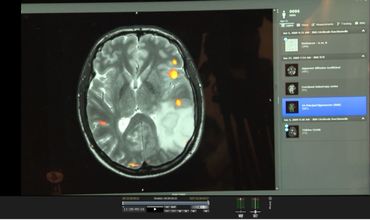

Depuis 2005, Laurent Hermoye et Wojciech Gradkowsky développent leur système qui combine les techniques les plus avancées de neuro-imageries. " Au-delà de l’image de l’IRM de base, notre logiciel ajoute la possibilité de voir des choses plus compliquées comme par exemple les zones du langage ou les zones motrices " détaille Laurent Hermoye, CEO d’Imagilys. Elles apparaissent clairement avec des codes couleurs sur l’image qu’on propose. Pour parvenir à ce résultat, il ne faut pas une image mais environ 3000 images. Donc ça veut dire que ces 3000 images qui sont acquises par la machine IRM, non seulement le radiologue n’a pas le temps de les regarder. Mais même s’il les regardait, il ne trouverait pas. Pour y arriver, il faut une analyse de traitement d’image et une analyse statistique. Et c’est précisément ce que fait notre logiciel. "

Ce logiciel permet en fait aux neuroradiologues d'établir une cartographie très précise du cerveau en vue d'une opération. L'hôpital Erasme à Bruxelles l'utilise depuis deux ans. " Avant, on utilisait le logiciel fournit par les constructeurs des machines IRM. Mais ce n’était pas satisfaisant car très compliqué à utiliser et surtout pas assez précis et pas suffisamment fiable explique Niloufar Sadeghi, cheffe du service de radiologie. " Avant, on ne pouvait pas bien localiser toutes les zones fonctionnelles, langage, vision, motricité etc. Et donc on n’enlevait pas le maximum de la lésion que ce soit une tumeur ou une malformation, de peur de toucher une de ces zones et de rendre le patient aveugle ou handicapé moteur. Or, au plus on enlève la lésion, au mieux le patient se porte après. Ce type de logiciel est donc une avancée importante en termes de soin pour le malade